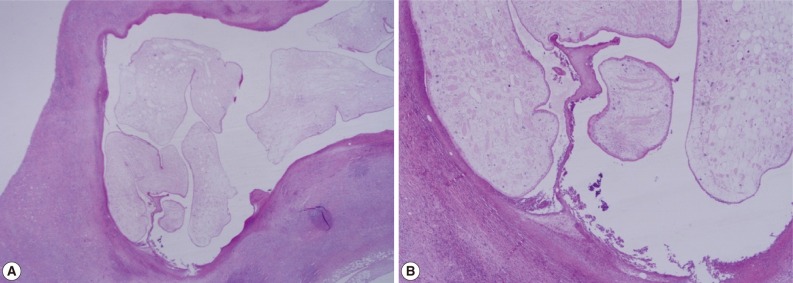

A 56-year old male visited our out-patient clinic for pancytopenia. Bone marrow biopsy and karyotype analysis showed myelodysplastic feature with 14% blast count and normal karyotype, indicating MDS, refractory anemia with excessive blast. He received 4 cycles of decitabine treatment during searching for matched unrelated donor, and partial response was shown. Allogeneic peripheral HSCT with myeloablative conditioning regimen consisting of busulphan and cyclophosphamide was performed from a HLA full-matched unrelated donor. However, at day 5 post-HSCT, 5 cm-sized hard and movable mass in the left scrotum and multiple palpable lymph nodes was detected at the left inguinal area. Pelvic magnetic resonance imaging and computed tomography were done and it was suspected initially as a myeloid sarcoma in the subcutaneous fat layer of the left scrotum and pathologic lymphadenopathy at the left inguinal area (Fig. 1). In order to confirm the diagnosis, gun biopsy was done on the left scrotal mass to avoid bleeding due to thrombocytopenia after HSCT. The result of the gun biopsy was inflamation of fibrovascular soft tissues with extensive interstitial eosinophilic infiltrations without evidence of malignancy. Persistent peripheral eosinophilia was also developed after HSCT. Subsequently, IgG antibody tests for paragonimiasis, cysticercosis, sparganosis, and clonorchiasis were done, and the results were positive for sparganosis and negative for all others. We re-evaluated the patient's past history and found out that he had swam in the river and ate raw fish, cow liver, and pork meat frequently when he was young. For a next step, excision biopsy was done as an approach for therapeutic diagnosis after recovery of thrombocytopenia. The cut surface of the biopsied specimen showed a cyst filled with whitish and myxoid tissues, measuring 2.0×0.6 cm (Fig. 2). The biopsy result was severe acute and chronic inflammation and fibrosis with a sparganum worm (Fig. 3). He was discharged after complete wound healing and stabilization of the post-HSCT condition.